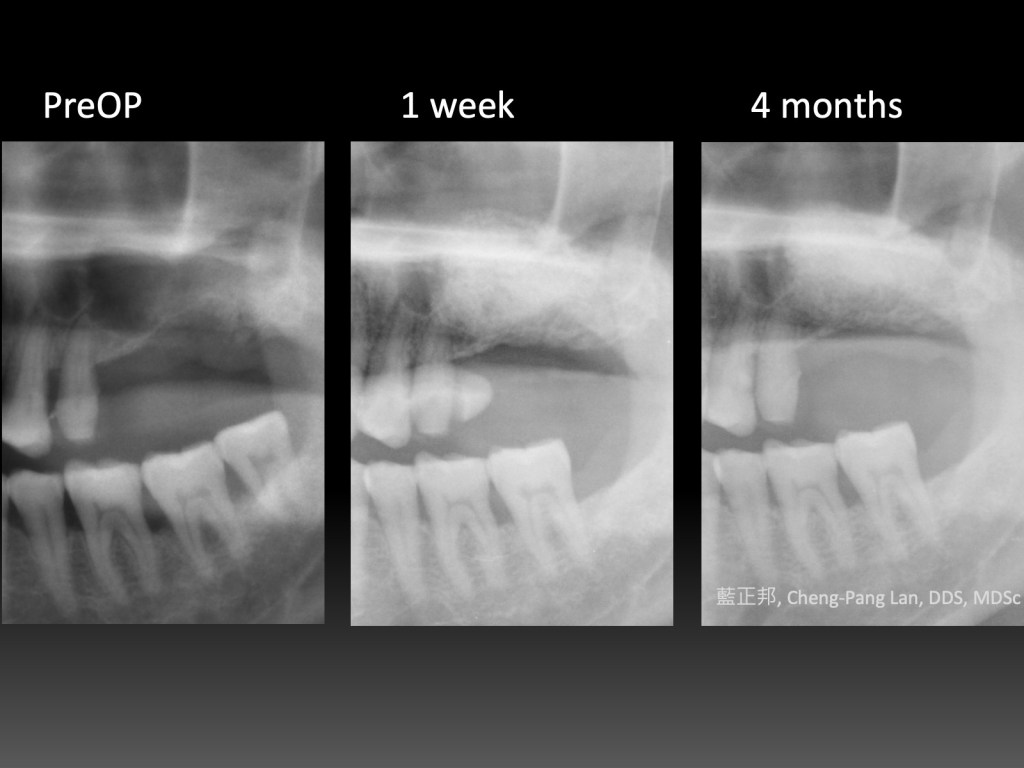

12 Years of Lateral-window Sinus Lift

2010年,台大第二年剛開始。這是我第一台鼻竇開窗手術,還記得很快地用骨刀切割,順利進入鼻竇。

但是翻到後面,遇到困難,只翻一半就遇到瓶頸,由台大老師接手翻完,之後回到我再放入材料並縫合。

這十二年來,口內狀態,加上X光檢查,一直都算穩定。但是回顧起來,病患其實血糖不低,加上抽菸,危險因子算多了。

如果其他的病患,危險因子一旦多,牙周穩定性會明顯變差,至少這個病患到現在為止還沒有。

到底是運氣好呢?還是有其他未知因素影響?又或許位於常態分佈—鐘型曲線兩端的極少數族群?

我也不知道。至少第一台十二年來慶祝一下~~